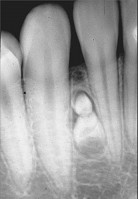

2.组图为牙瘤的外观及X 线表现,有关此病的描述错误的是 ( )![]() ![]() |